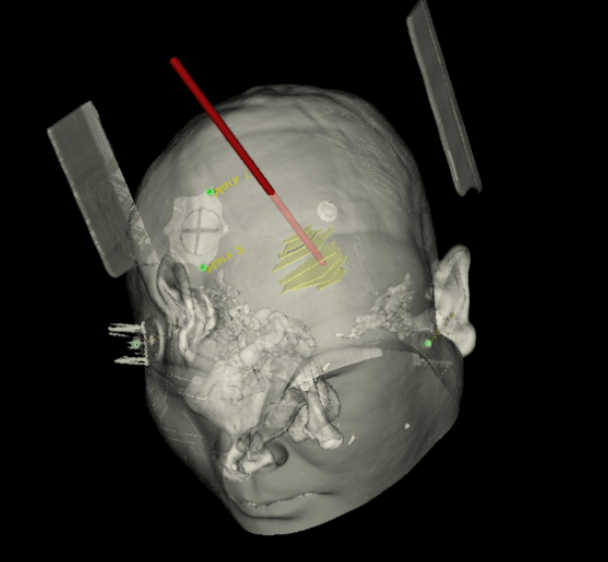

術(shù)前韓帥醫(yī)生使用“睿米”制定手術(shù)規(guī)劃

手術(shù)規(guī)劃在機(jī)器人軟件上制定完成